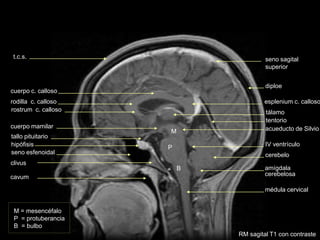

rostrum c. calloso

rodilla c. calloso

cuerpo c. calloso

clivus

seno esfenoidal

hipófisis

tallo pituitario

tentorio

seno sagital

superior

diploe

t.c.s.

acueducto de Silvio

RM sagital T1 con contraste

cuerpo mamilar

cavum

M = mesencéfalo

P = protuberancia

B = bulbo

M

P

B

médula cervical

amígdala

cerebelosa

IV ventrículo

tálamo

cerebelo

tubérculos

cuadrigéminos

espacio mamilopontino

circunvolución del

cuerpo calloso

agujero magno

RM parasagital T1 con contraste